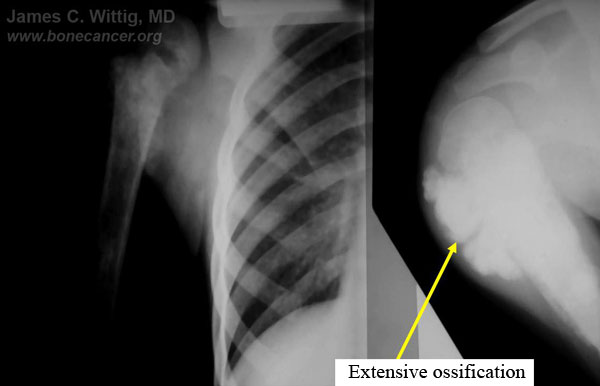

- Radiological studies may be useful in determining if the osteosarcoma has had a good response to chemotherapy preoperatively:

- X-rays and CT scans may show that intense ossification of the tumor occurs after a good response to preoperative chemotherapy

- The CT scan will often show a peripheral zone of calcification (egg shell around the tumor) when the tumor has had a good response